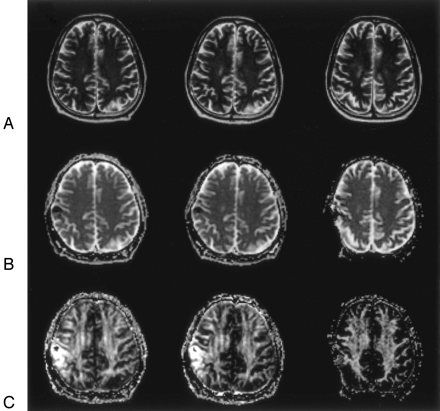

A 42-year-old male control subject. Three continuous section locations in the supraventricular plane.

A, WM segmented automatically from the reprocessed 3D SPGR T1-weighted images (1.9/9.2/1 [TE/TR/NEX]).

B, Reprocessed axial 3D SPGR images.

C, Isotropic ADC maps.

D, FA maps. Means of isotropic ADC and FA values of the pixels within the segmented WM of each hemisphere are calculated.

A 64-year-old man with total removal surgery for metastatic brain tumor, 30-Gy whole brain irradiation, and 15-Gy stereotactic radiosurgery (patient 5). The indices from only the left hemisphere were calculated because the right hemisphere had image distortion caused by the surgical procedure.

A, Axial T2-weighted images (TR/effective/TE/echo train length, 4000 ms/95 ms/18) at 4 (group 2; left), 8 (group 3, middle), and 12 months (group 4, right) following completion of radiation therapy show no abnormal intensity change in WM. At 12 months, slight increase in subarachnoid space of the right hemisphere is shown.

B, Isotropic ADC maps at 4 (left), 8 (middle), and 12 months (right) after completion of radiation therapy. Mean isotropic ADC values were 0.780, 0.707, and 0.720 (×10−3 mm2/s), respectively.

C, FA maps at 4 (left), 8 (middle), and 12 months (right) after completion of radiation therapy. Mean FA values were 0.32, 0.35, and 0.37, respectively. At 4 months after completion of radiation therapy, the mean FA value decreased and mean isotropic ADC value increased in comparison with the averages of mean FA value (0.38; SD = 0.02) and the mean isotropic ADC value (0.692; SD = 0.014) of the controls. The change of the indices appeared to resolve with time.